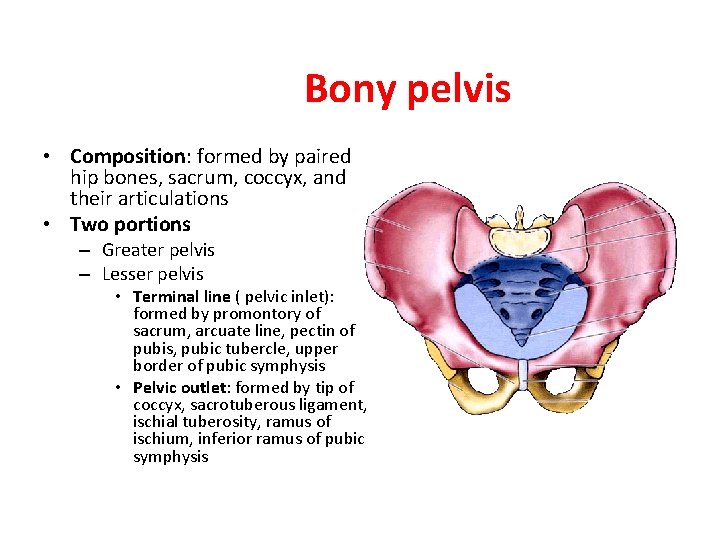

Bony pelvis • Composition: formed by paired hip bones, sacrum, coccyx, and their articulations • Two portions – Greater pelvis – Lesser pelvis • Terminal line ( pelvic inlet): formed by promontory of sacrum, arcuate line, pectin of pubis, pubic tubercle, upper border of pubic symphysis • Pelvic outlet: formed by tip of coccyx, sacrotuberous ligament, ischial tuberosity, ramus of ischium, inferior ramus of pubic symphysis